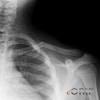

X-ray : 소아 쇄골 골절(Pediatric clavicle fracture)

소아 쇄골 골절의 진단

Single AP view

Medial clavicle : apical lordotic X-ray

CT scan